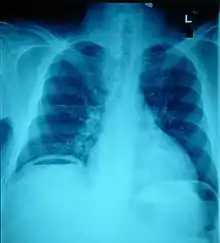

Ten percent of people with polytrauma who had no signs of abdominal injury did have evidence of such injuries using radiological imaging.[1] Diagnostic techniques used include CT scanning, ultrasound,[1] and X-ray.[7] X-ray can help determine the path of a penetrating object and locate any foreign matter left in the wound, but may not be helpful in blunt trauma.[7] Diagnostic laparoscopy or exploratory laparotomy may also be performed if other diagnostic methods do not yield conclusive results.[5]

The small intestine takes up a large part of the abdomen and is likely to be damaged in penetrating injury.[5] The bowel may be perforated.[4] Gas within the abdominal cavity seen on CT is understood to be a diagnostic sign of bowel perforation; however intra-abdominal air can also be caused by pneumothorax (air in the pleural cavity outside the lungs that has escaped from the respiratory system) or pneumomediastinum (air in the mediastinum, the center of the chest cavity).[4] The injury may not be detected on CT.[4] Bowel injury may be associated with complications such as infection, abscess, bowel obstruction, and the formation of a fistula.[4] Bowel perforation requires surgery.[4]